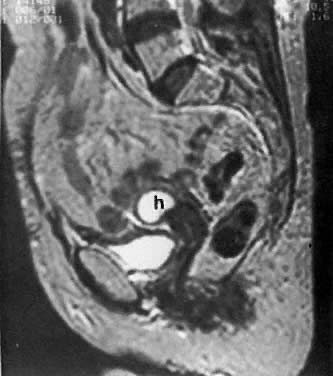

Fig. 6. Advanced cervical carcinoma. Sagittal ( A) and transverse ( B) sonograms of the pelvis show a markedly enlarged, irregular cervical mass invading both parametria ( black arrows ), encasing the right ureter laterally, and obliterating the fat planes ( white arrows) between the cervix and bladder anteriorly, and cervix and rectum posteriorly. The mass is obstructing the uterus, causing hydrometras. Sagittal sonogram ( C) of the right kidney shows moderate hydronephrosis. ( c, cervical mass; ur, ureter; b, bladder; h, hydrometras; k, kidney.)

The presence of hydrometras should raise the suspicion of cervical or endometrial carcinoma. It is best demonstrated by ultrasound (see Fig. 6A), but can be seen by both MRI (Fig. 7) and CT (Fig. 8).11,12 This finding, however, is nonspecific because it can also be seen in benign cervical strictures caused by either previous cervical inflammation (Fig. 9) or pelvic irradiation (Fig. 10).

Fig. 7. T2-weighted sagittal MRI of the pelvis shows cervical carcinoma ( c) causing hydrometras ( h ).